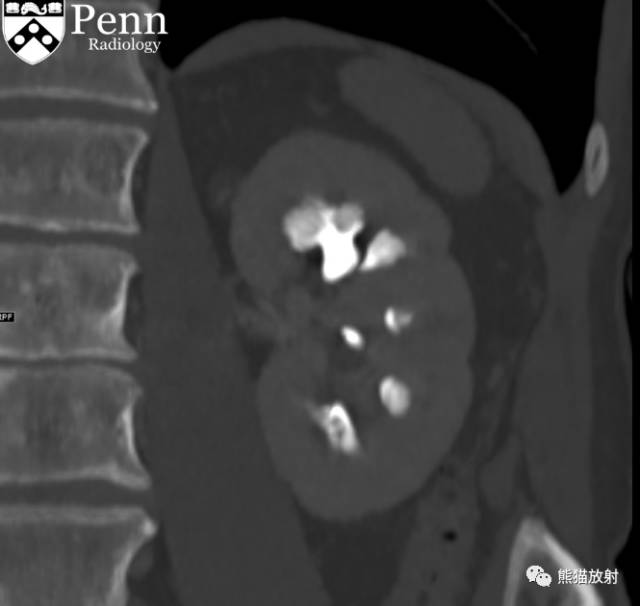

Scout, coronal precontrast, axial nephrographic/excretory phase images, and volume-rendered coronal reconstructions of the left and right kidneys are shown below.

定位像、冠状平扫、轴位排泄期图像及左、右肾冠状VR重建如下所示。

CT urogram (2017): Noncontrast images demonstrate multiple bilateral nonobstructing renal calculi, the largest measuring 6 mm in the right kidney. Some of the calcifications could represent nephrocalcinosis — for example, those in the upper pole of the right kidney. The kidneys show symmetric enhancement without suspicious renal mass. Multiple bilateral exophytic simple renal cysts are noted, the largest in the midpole of the right kidney measuring 3.6 x 4.3 cm. There are additional subcentimeter low-attenuation lesions that are too small to characterize. There is a “paintbrush sign” appearance to the renal medullae in keeping with a history of medullary sponge kidney. There is mild bladder wall thickening and trabeculation that may be related to chronic outlet obstruction. Further evaluation is deferred to cystoscopy.

CTU:CT平扫可见双肾多发非梗阻性肾结石,右肾最大者直径约6mm,其中一些钙化可能代表肾结石,例如,右肾上极的那些。肾脏对称性强化,未见可疑肾肿物。双肾可见多发单纯性肾囊肿,大者位于右肾中部,大小约3.6 x 4.3 cm;另可见不足1cm的低密度灶,其太小而不能显示。肾髓质表现为“毛刷征”,符合髓质海绵肾。膀胱壁轻度增厚并小梁形成,与慢性流出道梗阻有关。进一步评估需膀胱镜检查。